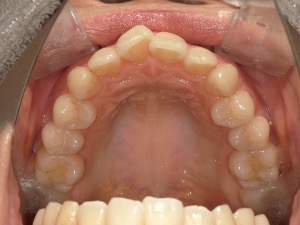

患者さんの年齢 20代 女性 症状 自分の歯が嫌い 治療内容 セラミック治療 費用 費用200万(税抜) 治療期間・回数 治療期間1ヶ月・通院回数3回 メリット 治療期間・回数が少ない デメリット・リスク 術後知覚過敏が起こる事ある - セラミック治療